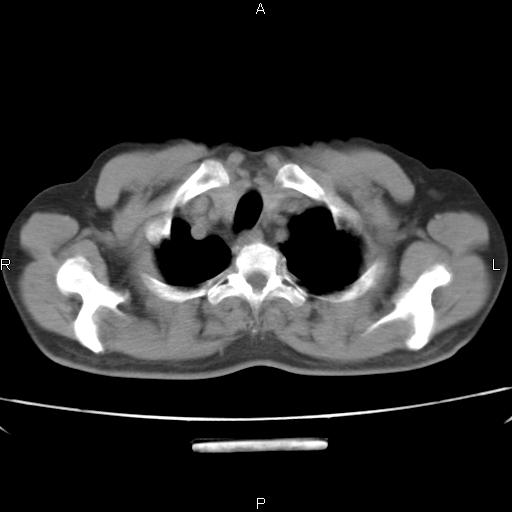

患者,男。50岁。近几日有咳嗽症状,无其他不适,既往病史无,考虑膈疝。请前辈们看看指导指导。

膈膨升,左下肺通气不良,膈肌好像还完整。

符合隔膨升,膈肌较完整。